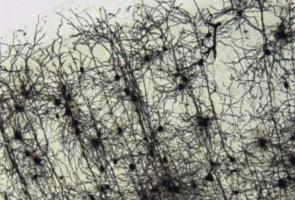

MALADIE de HUNTINGTON : Remplacer la glie pour retarder la maladie

MALADIE de HUNTINGTON : Le rôle clé du système cérébrovasculaire

Actualité publiée le 18/07/2024MALADIE de HUNTINGTON : Réparer la glie plutôt que les neurones